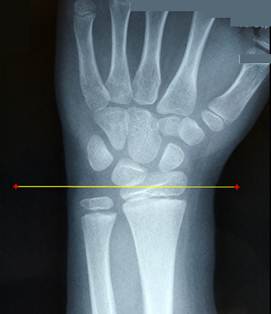

Снимок

описываемого больного слева, справа приведен снимок предплечья здорового ребенка

такого же возраста. Обратите внимание на соотношение уровней концов локтевой и

лучевой костей. На снимке слева заметен контур руки и её деформация (отмечена

стрелкой).